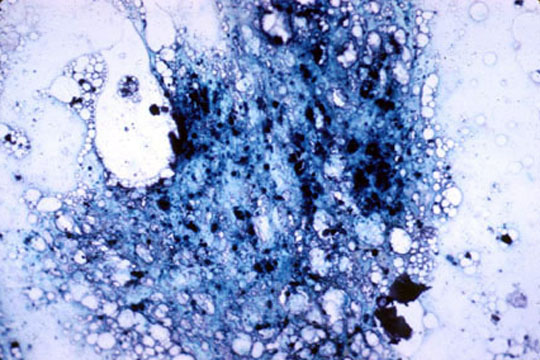

Bone marrow

- The cells shown here are all stages in the development of erythrocytes. Generally in the

red blood cell line: (1) the cells become progressively smaller, (2) the cytoplasm

changes from blue to pink, and (3) the nucleus ultimately is lost altogether. Cells shown here

include (in developmental order):

Top cell - proerythroblast

Lower row left = basophilic normoblast or erythroblast. It is still blue, but is smaller; the nucleus is more condensed

middle = polychromatophilic normoblast or erythroblast. Cytoplasm is grayer or muddier; nucleus is even more condensed.

right = orthochromatic (or eosinophilic) normoblast. Cytoplasm is pinker and cell is smaller; nucleus is pyknotic.

- The young cells in the r.b.c. line all have blue cytoplasm so the you to consider their size in identifying them.